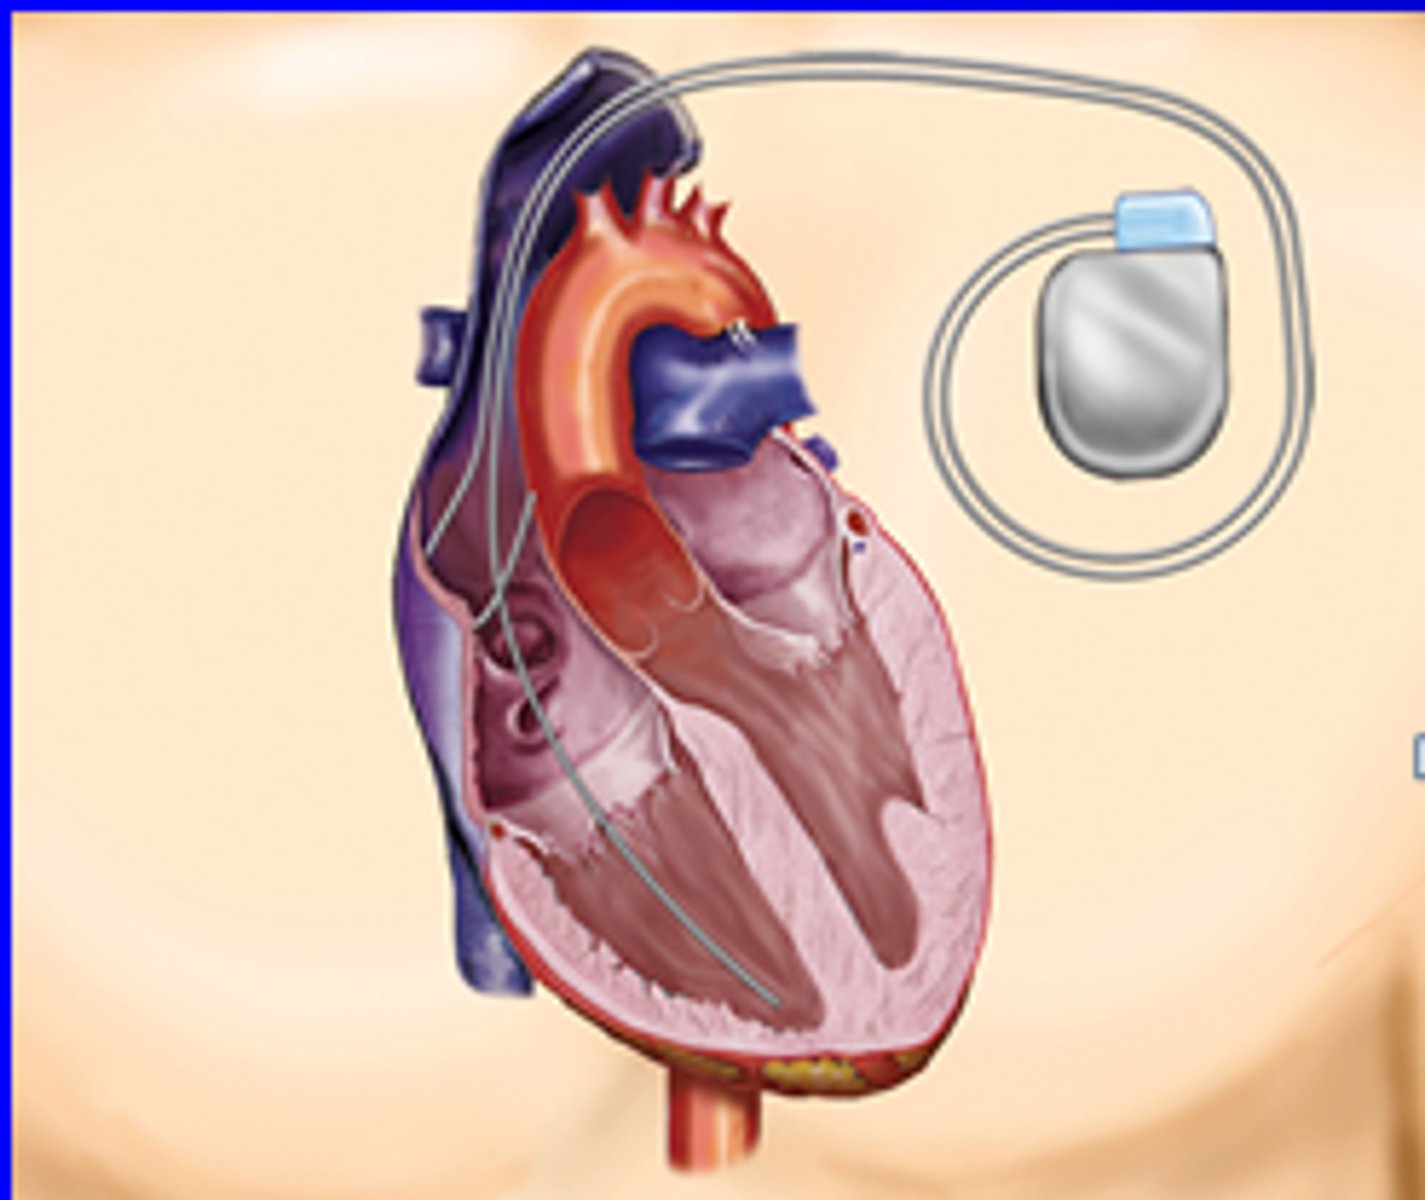

Artificial Cardiac Pacemaker

Implantable Cardioverter-Defibrillator

automatically terminates arrhythmia's by delivering low-energy shocks to the heart

Pacemaker

a small-battery powered device generally used to increase the heart rate by electrically stimulating the heart muscle

Cardioverter Defibrillator (ICD)

device that detects sustained ventricular tachycardia or fibrillation and delivers a low energy shock to the heart, restoring the normal rhythm